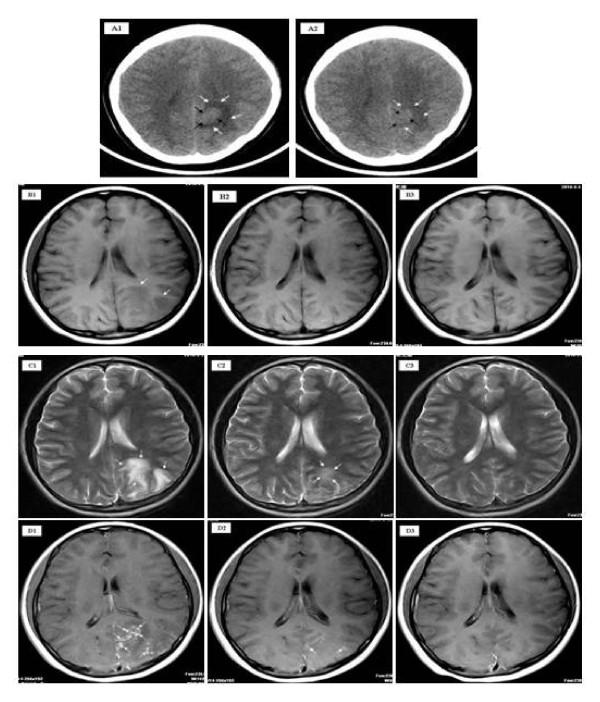

MRI in cerebral schistosomiasis: characteristic nodular enhancement in 33 patients.